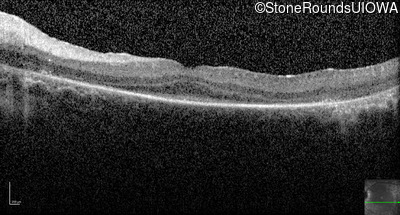

Optical Coherence Tomography - Right -

No Light Perception

Exemplar

Optical Coherence Tomography - Left -